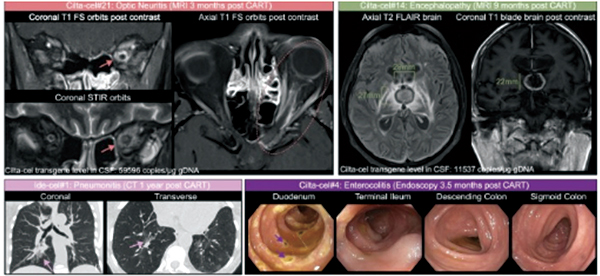

在西达基奥仑赛治疗者中,最常见的CirAE为脑神经麻痹(8%)、肠炎(5.6%)、帕金森病(4.8%)和关节炎(1.6%),而迟发性免疫效应细胞相关神经毒性综合征(ICANS)、脑病变和周围神经病变则较少见(各0.8%)。2例患者在西达基奥仑赛治疗下出现多次CirAE,其中1例74岁男性患者发生3例次不同的CirAE。ide-cel治疗中唯一被观察到的CirAE为肺炎。